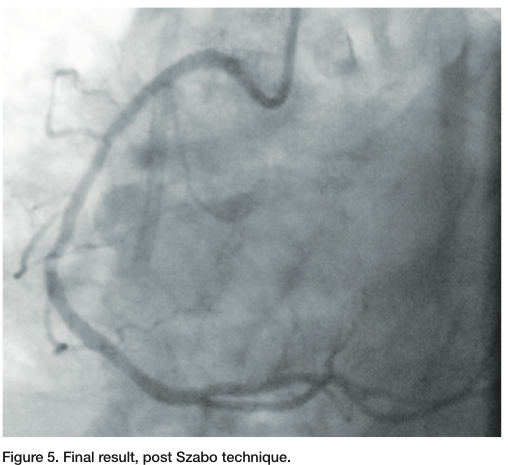

using the Szabo technique1 (Figures 2-3), with a second wire placed in the aortic root to ensure ostial placement (Figure 4). The stent was then advanced to the ostium, deployed, and then the second wire was removed from the proximal strut, ensuring that we were ostial in placement. We post-dilated with a 3.75mm Quantum balloon (Boston Scientific) at high pressure. Final angiography revealed TIMI-3 flow without any dissection, perforation, or embolization. The patient tolerated the procedure well.

One of the primary objectives of treating ostial lesions is the correct placement of the stent to optimize lesion coverage and avoid geographic miss. Ostial lesions are associated with increased restenosis, even in the drug-eluting stent era.2 This is due in part to lesion rigidity, calcification and elastic recoil. Angiographic determination of accurate stent placement has limitations and various techniques, and devices have been proposed to facilitate accurate placement. The Szabo technique uses a second wire through a trailing strut to allow for accurate stent placement. This technique appears to obviate the limitations of angiographic placement and does not require any adjunctive devices.

The technique was first described by Szabo et al in 2005 and involves a second guide wire placed in the aorta (or branch vessel for a non aorto-ostial lesion) to anchor the stent.1 The stent is prepared by a low pressure inflation (1-2 atm) with the protective sleeve left in place while exposing the proximal struts. The remainder of the stent is compressed with the sleeve. The wire is passed through the proximal strut of the stent followed by crimping of the “lifted” strut; however, not to the degree that the anchor wire is not mobile. The stent then travels over the primary guide wire and the anchor wire, which stops forward motion of the stent at the

vessel ostium (Figures 2-3).3 The stent is then deployed at low or nominal pressure, followed by removal of the anchor wire. The stent balloon can then be reinflated or another balloon can be used to post dilate.